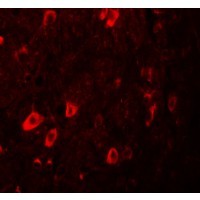

- Experimental details

- Immunofluorescence of ZBTB3 in human brain tissue with ZBTB3 antibody at 20 ug/mL.

- Validation comment

- IF